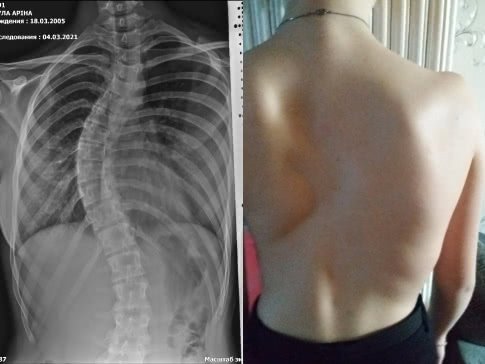

Путь начали с Областной детской больницы. Рентген позвоночника и дополнительные обследования показали, что угол искривления составляет 36 градусов. Длительное время доктор наблюдал динамику и уверял, что ухудшения нет. Но боли в позвоночнике продолжали мучить Арину, движения все больше ограничивались, стали страдать внутренние органы.

Состояние резко ухудшилось после падения. В Клиническом центре им. Руднева врачи определили, что сколиоз достиг уже 3 степени: заболевание очень быстро прогрессирует. Угол искривления позвоночника в верхнем отделе составляет 53 градуса, в нижнем - 30. По рекомендации врача семья отправилась в Харьков на консультацию к специалистам. Доктора сошлись во мнении, что Арине срочно требуется операция по выпрямлению позвоночника специальной конструкцией. Была озвучена сумма в 133 131 грн.

ФИО: Тула Арина Дмитриевна

Дата рождения: 18.03.2005

Диагноз: сколиоз грудного и поясничного отдела позвоночника 3 степени